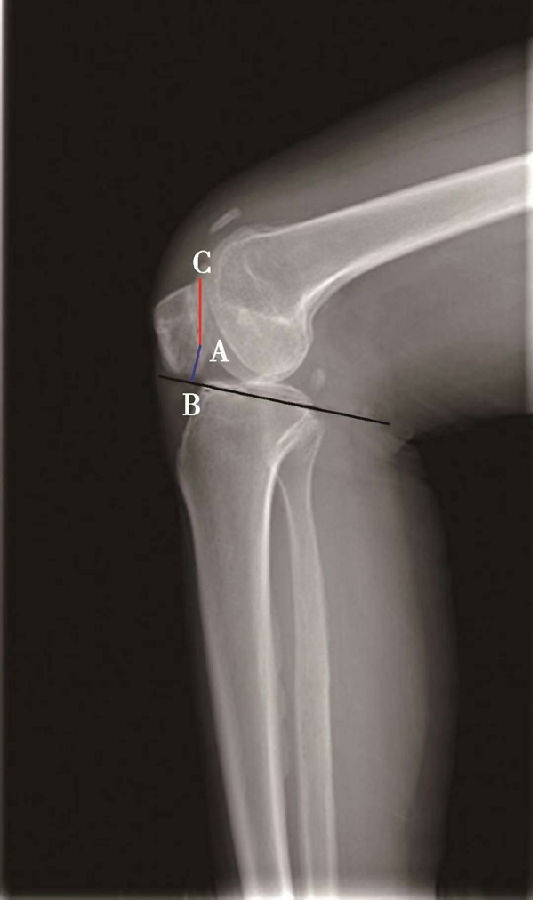

(2)Insall-Salvati指数>1.2意味着高位髌骨(图5),<0.8意味着低位髌骨(图6)。

体位:侧卧位屈膝20°~70°。

如图示:AB是髌韧带长度,AC髌骨纵轴长度。Insall-Salvati指数=AB/AC(图4)。

图4 Insall-Salvati指数 =AB/AC=1.10,为正常髌骨高度

图5 Insall-Salvati指数=AB/AC=1.40,为高位髌骨

但是此法测量髌骨韧带时往往依赖准确的估计胫骨结节与髌骨下极的位置。因此,髌骨下极和胫骨结节的病变都会影响测量的结果,尤其是发生胫骨结节骨软骨炎的患者确定这一位置便更加的困难。此外,该指数不能用于评估胫骨结节向近端或远端移位的效果。因为该指数测量所使用的标记在胫骨结节术后均未发生改变,Insall指数也就不会变化。

图6 Insall-Salvati指数 =AB/AC=0.67,为低位髌骨